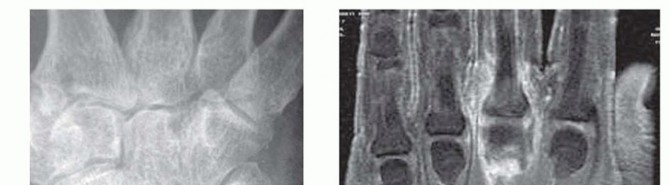

Radiographic evaluation begins with orthogonal plain films. Early in the disease process, radiographs are typically normal or demonstrate only subtle soft tissue swelling and joint space widening secondary to effusion. However, they are crucial for ruling out retained radiopaque foreign bodies, fractures, or underlying chronic arthropathies. The presence of chondrocalcinosis, for instance, may suggest pseudogout, though crystalline arthropathy and septic arthritis can coexist.

When the diagnosis remains equivocal, or to assess the extent of soft tissue and osseous involvement, Magnetic Resonance Imaging (MRI) is the modality of choice. MRI provides unparalleled soft tissue contrast, readily identifying joint effusions, synovial hypertrophy, and early marrow edema indicative of impending osteomyelitis. T2-weighted fluid-sensitive sequences will dramatically highlight the intra-articular purulence and surrounding inflammatory edema.